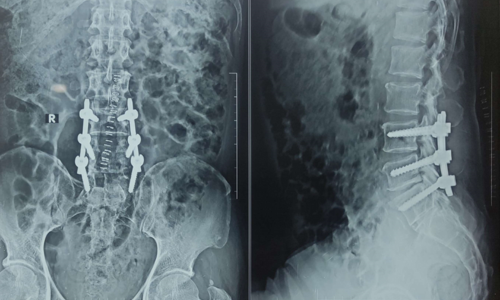

Posted on Nilesh KaduTrustindex verifies that the original source of the review is Google. I visited Dr. Nitish Agarwal for my severe back pain and shoulder issue. He checked my MRI very carefully and gave the perfect diagnosis. Yesterday, he performed the procedure (Root Block and Shoulder Injection), and it was completely painless. He is an expert and targeted the exact nerve point causing the trouble. Very helpful and humble doctor. Highly recommended for anyone with spine problems.Posted on Raju GorkhaTrustindex verifies that the original source of the review is Google. I was unable to make movement and suffered from right foot drop which is equal to halfway paralysis. Dr. Nitish Agarwal performed very fine microscopic surgery on L3, L4 & L5. After 90 days under his treatment I could go for a walk min. 6 kms a day, I have started my regular activities after 120 days. Thank you so much Dr. Nitish Agarwal sir.Posted on Pururaj GuravTrustindex verifies that the original source of the review is Google. I was suffering from severe back pain, and Dr. Nitish Agrawal has been extremely supportive throughout my treatment. He listened carefully, explained everything clearly, and guided me very well. His treatment has really helped me recover. He is one of the best spine specialists — highly recommended!Posted on Vinal AgrawalTrustindex verifies that the original source of the review is Google. I had consulted many doctors before Dr Nitish for my mother's spine issue,most recommended complex procedures and surgeries. Fortunately we found Dr Nitish and it has been life changing for my mother,she was in immense pain before the simple surgery he did. It's rare to find a surgeon who explains everything in detail and provides such exceptional care even after the surgery. I Would highly recommend him.Posted on Ajinkya MohadkarTrustindex verifies that the original source of the review is Google. My mother had sustained a fracture to her right hand wrist and we were worried about her recovery due to age factor. One of our family Doctor referred us to Dr. Nitish Agrawal and we visited Dr. Nitish Sir. Dr. Nitish sir ensured that my mother don't need a surgery and treated her by application of plaster (temporary and then cast-iron or Firm plaster) with certain orthopaedic treatment to hand and prescribed oral medication for ensuring recovery is faster without any surgery. Attaching the photo of xray which shows recovery of wrist bone which has rejoined and we are still continuing treatment to ensure my mother is fully recovered and is fit. Thank you Dr.Nitish Agrawal for your support.Posted on Samadhan LokhandeTrustindex verifies that the original source of the review is Google. Hi everyone, myself Samadhan. I was suffering from severe spine pain for a long time, and one of my friends suggested I visit Dr. Nitish Agarwal. Honestly, that was the best advice! Dr. Nitish listened to my problem very patiently, explained the cause in detail, and gave me the right treatment. I started feeling better within a short time. He is very polite, knowledgeable, and truly cares for his patients. I highly recommend Dr. Nitish Agarwal for anyone dealing with spine or back pain. Thank you, doctor, for your excellent treatment and support!Posted on POOJA JAGDALETrustindex verifies that the original source of the review is Google. Dr. Nitish Agrawal is an excellent spine specialist who patiently listens, explains the problem clearly, and provides the best treatment options.Posted on vipul pardeshiTrustindex verifies that the original source of the review is Google. Dr.Nitish sir is an incredible surgeon. I had excellent results from my recent spine surgery. The entire process, from consultation to recovery, was handled with professionalism and care. The outcome has been life-changing. I highly recommend Dr.Nitish agarwal to anyone in need of a spine surgeon.Posted on Deepak JadhavTrustindex verifies that the original source of the review is Google. A few months back I took treatment for my back pain from dr. Agarwal sir ...last 7-8 years i was suffering with low back pain,unbale to stand for more than 10 minutes..My low back hurts continuously, and also left leg pain was unbearable....i try every possible way of treatment from various suggestion...After several treatment...one of my relative suggested dr. Nitish Agarwal sirs name then I visited Dr. Nitish Agarwal sir in clinic. He suggested me x ray and MRI. On that basis he advise me caudal Block with root block with facet block for pain management. After block my pain goes with in a week. He advise me regular Physiotherapy at home. Now after regular exercise I am pain Free. Dr. Nitish Agarwal is a good doctor for any spine related problem.... Thank u dr. Agarwal Sir 🙏Posted on Kumar BTrustindex verifies that the original source of the review is Google. My wife had major infection in neck and lower back. She was bedridden. her legs and hands were weak. Then we admit her under Dr. Nitish Agarwal sir and did MRI. He explained that she is having major infection in cervical and lumbar spine. Due to infection her spinal cord is compressed so she was not able to walk. Then sir did operation for neck and removed infected tissue and spinal cord is freed and put a plate. Her lower back is treated with medicine only. She was given 2 months antibiotics by saline and 5 months oral antibiotics were given. He also advised regular exercise. After 15 days of surgery she started walking with support. Now after 1 year she is completely alright and walking like a normal person. She is regularly doing all her activities. Now she can also travel by 2 wheeler. Thank you to Dr. Nitish Agarwal sir for his expert work in spine. I recommend Dr. Nitish Agarwal for any spine related problem.